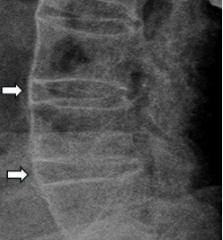

此症狀較常發生於年輕的患者,常因腰椎彎腰負重過度造成椎間盤上下壓力增加而往後膨出甚至突出壓迫到椎間神經根而常併有下肢疼痛酸麻現象,尤其在咳嗽、打噴嚏或彎腰提重物等狀況下,脊椎受壓增加之瞬間容易誘發坐骨神經痛的症狀 (Song, 2017:60558-60567; Tonosu, 2016: e0166031)。(參見圖 1)

圖 1 第三四腰椎間盤凸出(如箭頭所示)